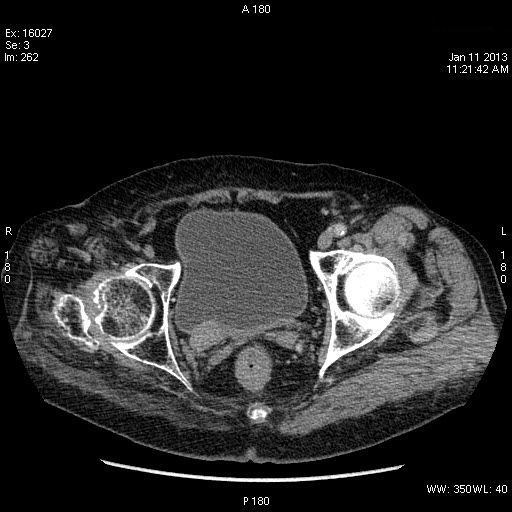

Пожилой человек с аневризмой брюшного отдела аорты.

Да, переходноклеточная опухоль нижней трети правого мочеточника, вторичный гидроуретеронефроз.

КТ

se001.jpg

se002.jpg

se006.jpg